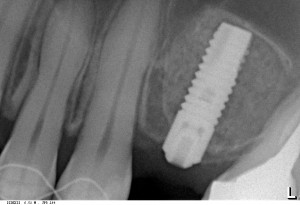

Сегодня, очень кратко, в виде анонса: имплантация и синуслифтинг в области 26 зуба. Вся операция от разреза до последнего шва заняла 25 минут.

Исходная ситуация:

Используем имплантат Astratech Osseospeed 4.0×11 mm:

Вот в этом вся суть имплантологии. Нужно поставить имплантат нужного размера в нужное положение. На левом снимке видно, что имплантат уперся в костный фрагмент, который мы поместили в субантральное пространство заранее, поэтому он не повредит слизистую оболочку пазухи, даже если мы этого очень захотим.

Длина и диаметр импланта выбирается, исходя из размеров удаленного зуба. Еще одно правило.

Обратите внимание, что полированнаяя фаска у шейки импланта находится выше уровня костной ткани.

И контрольный снимок:

На мой взгляд, по снимку всё очень-очень понятно. Вся операция — как в детской книжке.

Напомню, что заняла она, примерно, 25 минут. От начала до конца.